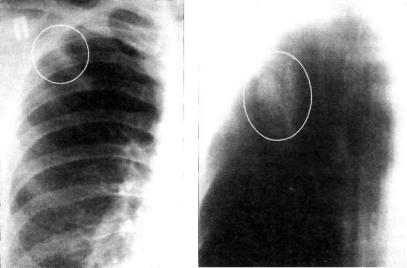

Симптомы и лечение инфильтративного туберкулеза легких

Раздел: Снимки-откровения